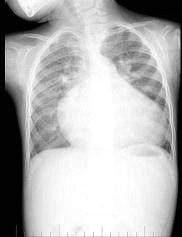

问题 男性,1岁零8个月,生长发育差,易患呼吸道感染,心悸气促,行心脏正、侧位片检查如图所示,正确的描述和结论是 ( )

选项 A、房间隔缺损 B、室间隔缺损 C、肺纹理增多 D、侧位示心前间隙变窄,心后食管前三角间隙消失 E、正位示心影向两侧扩大,心尖左移

答案 BCDE